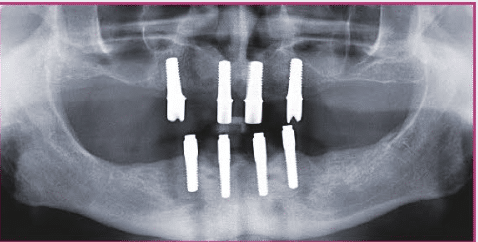

Nach entsprechender klinischer und röntgenologischer Diagnostik (Abb. 1a, b) wurden vier zweiteilige Keramikimplantate (Pure Ceramic, Straumann Group) für die Insertion im Oberkiefer Nach komplikationsloser dreimonatiger Osseointegration geplant (Abb. 2). Der Entscheidung bei der Auswahl dieser Medizinprodukte lag auch der Umstand zugrunde, dass die Implantate für systemimmanente Scanbodies kompatibel sind undüber sollte im digitalen Workflow hergestellt werden. Hierfür wurden zunächst die zum Implantatsystem passenden Scanbodies die sich schon bei der einteiligen Variante des Keramikimplantates (Monotype Pure Ceramic, Straumann Group) seitJahren auf dem Intraoralscanner (iTero, Align) digitalisiert (Abb. 5a).

Voraussetzung für die dauerhaft gute Funktion von Doppelkronen ist die exzellente Passung der beiden „Partner“ (Zirkonoxid-Kappe und Galvano-Kappe) (Abb. 5b). Die hochglatten Flächen der Zirkonoxid-Kappen bildeten die Basis für den Galvanisierungsprozess. Im digitalen Workflow bleibend, wurde das Tertiärgerüst im Laser-Melting-Verfahren hergestellt und intraoral die Galvano-Kappen im Gerüst verklebt. Die Passivierung im Mund gilt als Voraussetzung für die langzeitstabile Funktion der teleskopierenden Brücke. Nach erneuter Bissnahme und Kieferrelationsbestimmung sowie einer Ästhetikeinprobe konnte die Restauration fertiggestellt und in der Praxis eingegliedert werden (Abb. 6-12). Großer Vorteil des beschriebenen digitalgestützten Vorgehens: Der Patient musste zu keiner Zeit mit einer Silikonabformung „belastet“ werden. Bis auf die ästhetisch-funktionelle Umsetzung konnte komplett im digitalen Workflow gearbeitet werden.